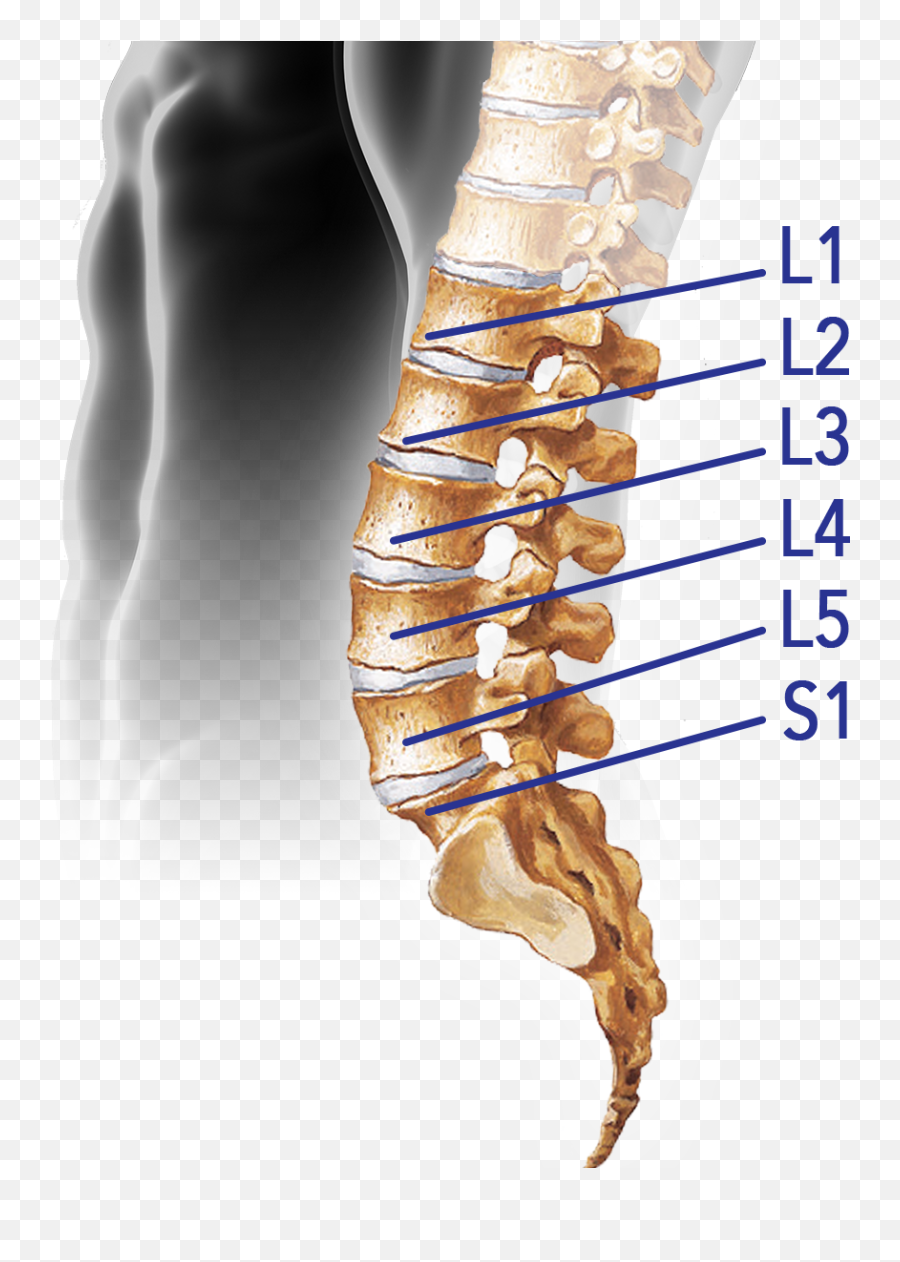

Структура позвоночника: сегменты и тазовые отделы в фотографиях